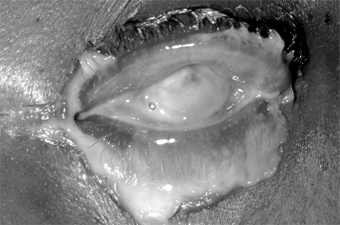

1. Hyperacute (and subacute) bacterial conjunctivitis-Purulent conjunctivitis-

(caused by N gonorrhoeae, Neisseria kochii, and N meningitidis) is marked by a profuse purulent exudate (Figure 5-1). Meningococcal conjunctivitis may occasionally be seen in children. Any severe, profusely exudative conjunctivitis demands immediate laboratory investigation and immediate treatment. If there is any delay, there may be severe corneal damage or loss of the eye, or the conjunctiva could become the portal of entry for either N gonorrhoeae or N meningitidis, leading to septicemia or meningitis.

Figure 5-1

Figure 5-1: Gonococcal conjunctivitis. Profuse purulent exudate. (Courtesy of L Schwab.)